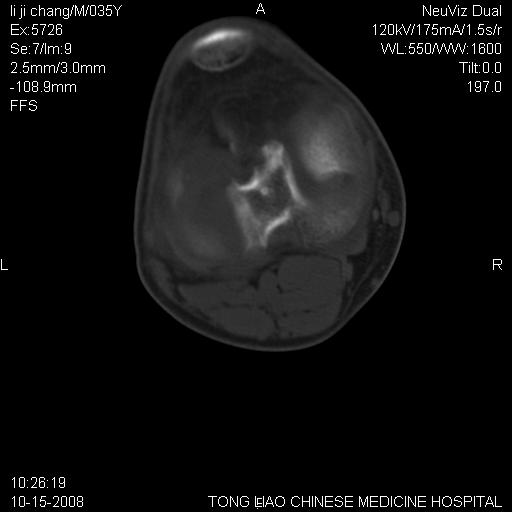

男,35岁,骨科诊断骨性关节炎。继往使用过激素,现股骨头坏死。膝关节病变,请会诊

一元论-----亦考虑为坏死

支持考虑无菌坏死

支持无菌坏死伴退行性骨关节病.

剥脱性骨软骨炎:是一种关节下软骨及软骨下骨缺血性坏死。

支持 无菌性坏死伴退行性骨关节病。